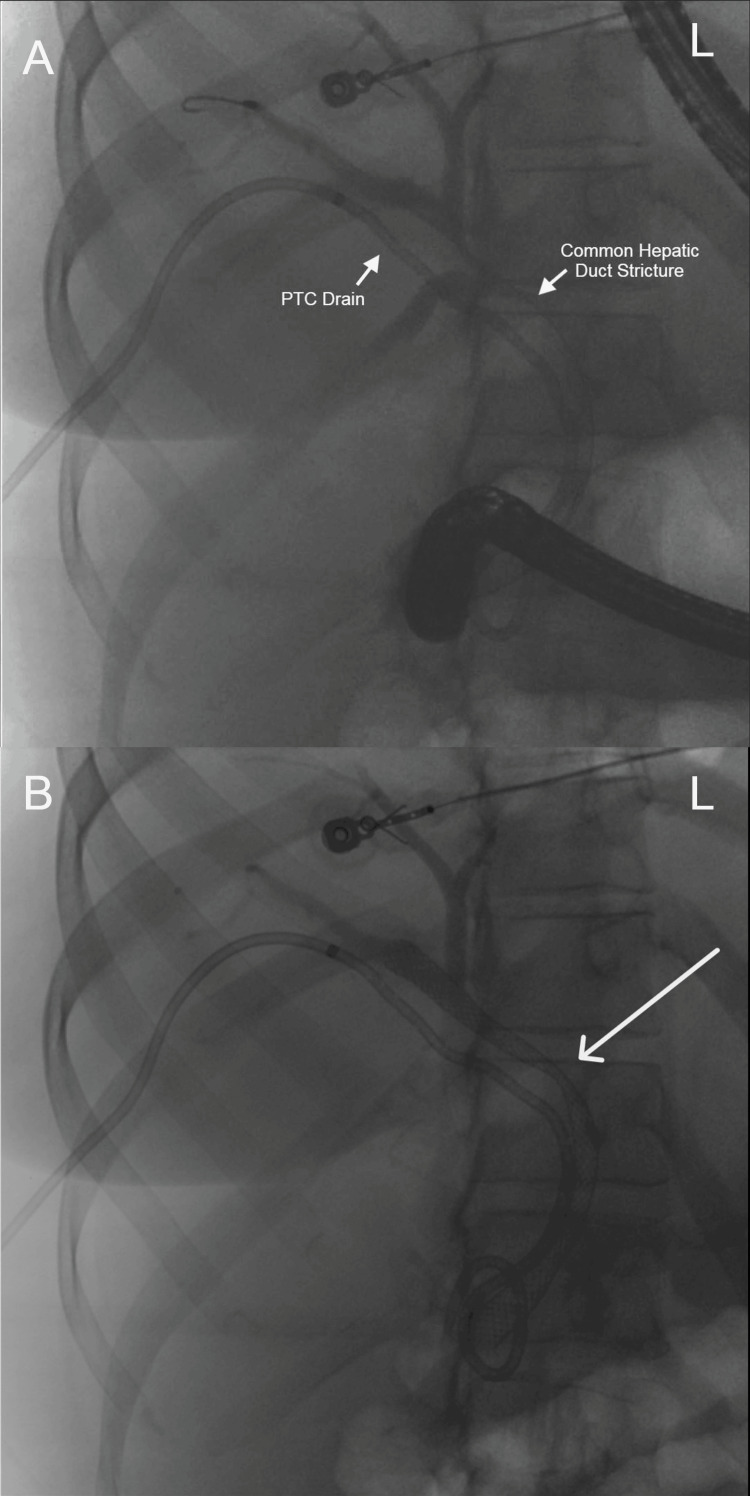

Abdominal computed tomography (CT) with IV contrast showed multiple peripherally enhancing masses within the liver, as well as bilateral intrahepatic biliary ductal dilation (Figure 1). Endoscopic ultrasound revealed multiple large solid masses in the liver consistent with metastases and excluded a fluid component, i.e., abscess. Due to the acute cholangitis, endoscopic retrograde cholangiopancreatography (ERCP) was performed, and the PTC drain was visualized emerging from the major papilla. The common bile duct was then cannulated using a balloon adjacent to the PTC drain, and contrast was injected. The cholangiogram showed a normal CBD and a mild stricture in the common hepatic duct, but the PTC drain was in an entirely separate ductal system (Figure 2A). A metal stent was then placed into the CBD and extended from the common hepatic duct to the major papilla (Figure 2B). The metal stent emerged from the major papilla adjacent to the PTC drain (Figure 3). Due to concern about the misplacement of the PTC drain, the interventional radiology (IR) team interrogated the drain using contrast (Figure 4). This revealed the presence of a DCBD, with the PTC drain placed in the right CBD and an endoscopically placed metal stent in the left CBD. Consecutive images from the contrast study showed a single proximal communication between the two CBDs. The IR team then removed the PTC drain, and a metal stent was placed in the right CBD, with both stents joining at the major papilla, thus confirming the presence of type Vb DCBD (Figure 5). Following the placement of both metal stents, the patient’s serum bilirubin levels normalized, and symptoms improved to where she was safely discharged home to continue her palliative chemotherapy regimen with her oncologist. Upon following up with her oncologist, her serum bilirubin was 1 mg/dL. The patient ultimately elected to pursue home hospice care shortly afterward.